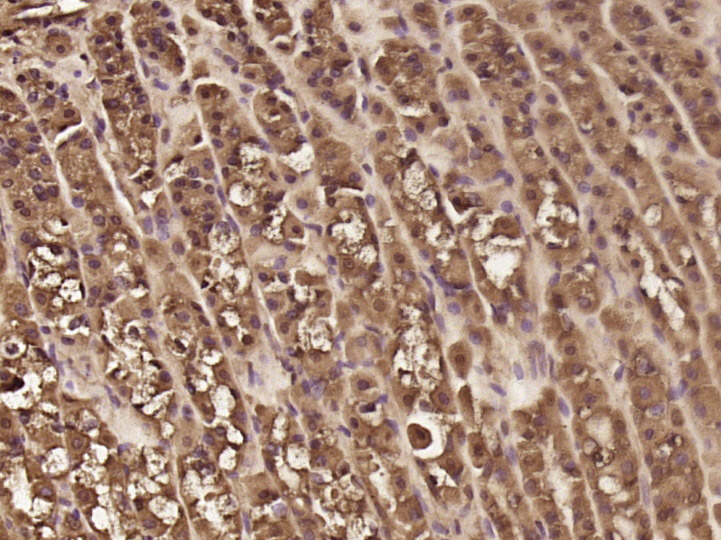

Paraformaldehyde-fixed, paraffin embedded (rat stomach tissue); Antigen retrieval by boiling in sodium citrate buffer (pH6.0) for 15min; Block endogenous peroxidase by 3% hydrogen peroxide for 20 minutes; Blocking buffer (normal goat serum) at 37°C for 30min; Antibody incubation with (PPP1R11) Polyclonal Antibody, Unconjugated (bs-19989R) at 1:400 overnight at 4°C, followed by operating according to SP Kit(Rabbit) (sp-0023) instructionsand DAB staining.